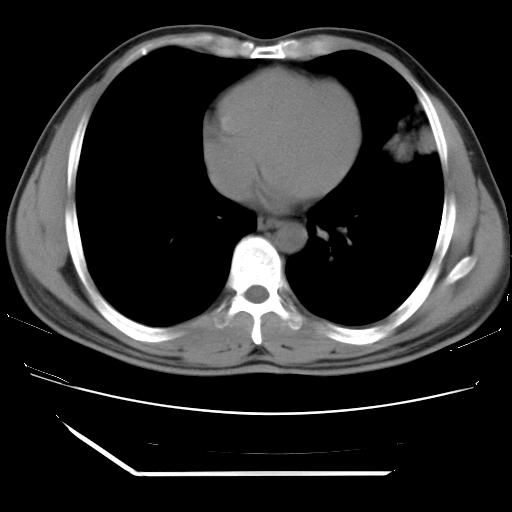

男,38岁,于2009年8月9日晚突发左侧胸痛,今x线提示左下肺阴影,为了明显确诊断,行ct检查,

血常规:嗜酸性细胞增高,单核细胞增高。

纵膈窗

病灶发生在下叶,密度均匀,边缘模糊、毛糙,周围血管纹理增强扭曲改变,靠近胸膜处病灶胸膜反应明显。

支持考虑---球形肺炎。

左肺舌叶病变。主体病灶呈类圆形中心密度低,成液化趋势周边班片影分布

考虑肺脓肿

虽然实验室检查支持炎性病变,且病变内有坏死改变(中央呈大片状低密度影),但仍不能掉以轻心,鳞癌也可以有这种影像改变。